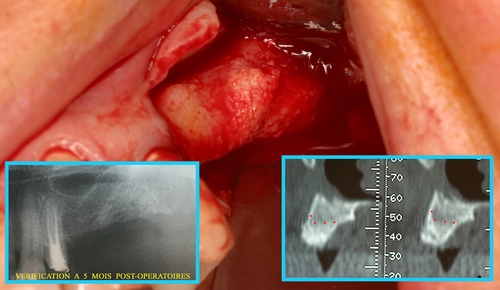

Un rayonnement laser pénétrant utilisé sous eau oxygénée à 10 volumes permet de décontaminer tout l’os du maxillaire après l’extraction des dents (fig. 30)

Fig. 30

Décontamination du maxillaire après extractions

Cela permet d’envisager immédiatement une régénération osseuse qui est effectuée le jour même des extractions et le résultat à 5 mois postopératoires (fig.31) montre une régénération complète du massif osseux.

Fig. 31

Régénération osseuse du maxillaire